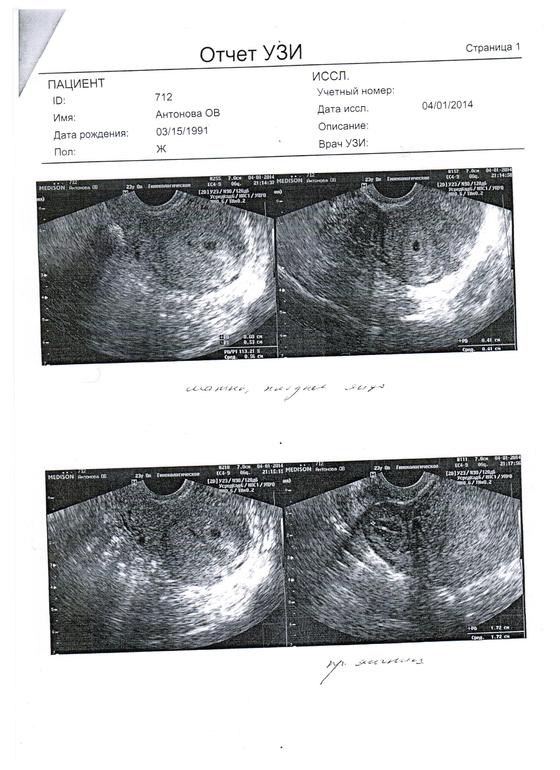

Через неделю пошла на УЗИ и здала ХГЧ=)))))

УРРРРААААААА!!! ПЯ есть!!!! Но ещё совсем маленькое... Но опять всё не ладно((( Отслойка маленькая(((( Я испугалась, давай врача доставать, есть ли шанс??? Он сказал что есть, но опять же не факт, что там эмбрион есть. Тааак вооот, вышла я от врача опять в терзаниях, что делать??? Приехала домой, и решила вызвать скорую!